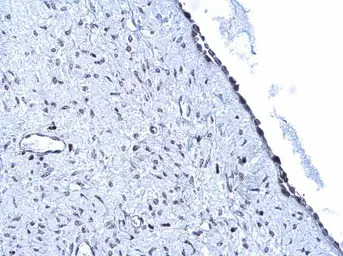

ARID1A antibody detects ARID1A protein at nucleus by immunohistochemical analysis.

Sample: Paraffin-embedded human lung cancer.

ARID1A stained by ARID1A antibody (GTX129433) diluted at 1:500.

Antigen Retrieval: Citrate buffer, pH 6.0, 15 min